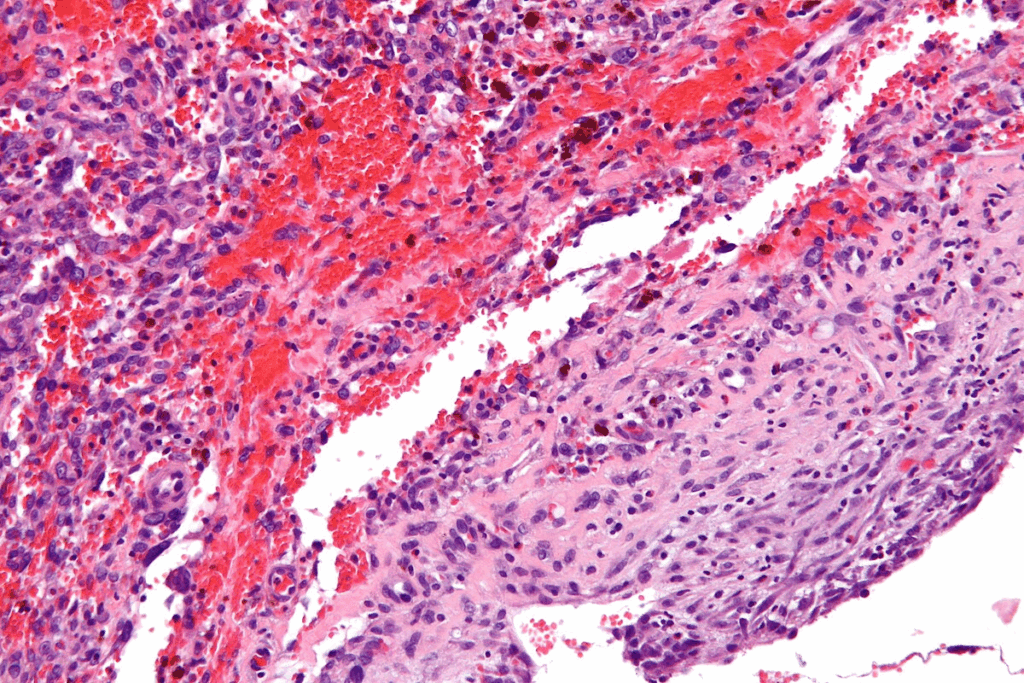

Uterine fibroids are non-cancerous growths in or around the uterus. They affect women’s health. These growths vary in size, number, and location. Their impact on a woman’s life can be big.

Uterine fibroids, also known as leiomyomas, are benign tumors in the uterus. They are made of extra muscle and fibrous tissue. Hormones, like estrogen, help them grow.